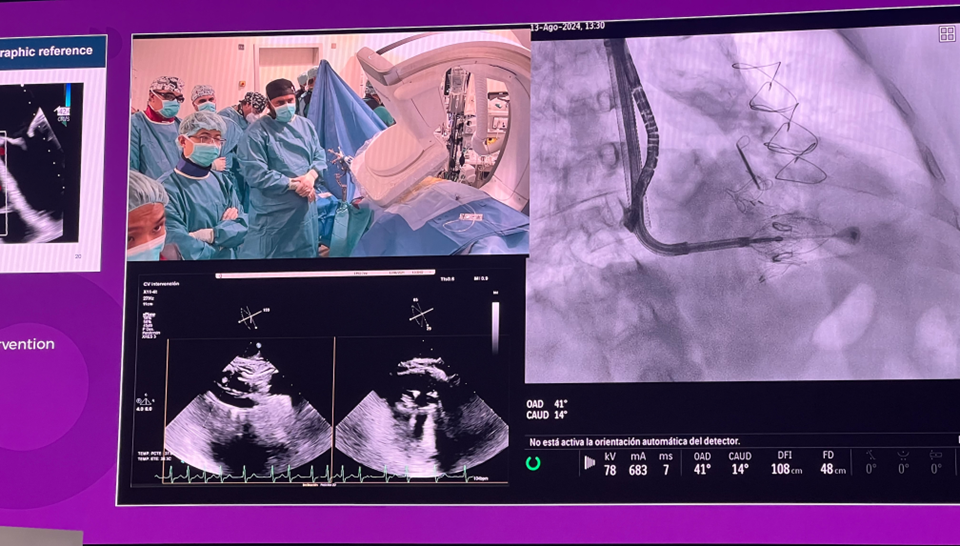

隨后由來自西班牙維哥-阿爾瓦羅昆奎羅醫(yī)院(Hospital Álvaro Cunqueiro, Vigo, Spain)的 Rodrigo Estevez-Loureiro 教授在大會主會場的經(jīng)導管介入瓣膜新技術(shù)環(huán)節(jié),帶來了一例 LuX-Valve Plus 手術(shù)錄播,對手術(shù)植入的步驟和關(guān)鍵要點進行了詳細深入的介紹。同時,臺上的多位討論嘉賓也結(jié)合他們的 LuX-Valve Plus 手術(shù)經(jīng)驗進行了深入的探討。來自香港瑪麗皇后醫(yī)院(Queen Mary Hospital, Hong Kong, China)的 Simon Lam 教授分享了 LuX-Valve Plus 在術(shù)前有起搏導線病人中的植入經(jīng)驗,來自巴西圣保羅(Rede D'Or São Luiz, São Paulo, Brazil)的 Vinicius Esteves 教授補充了 LuX-Valve Plus 獨特的非徑向支撐力設計,能夠?qū)崿F(xiàn)非常低的術(shù)后起搏器植入率,來自法國波爾多大學醫(yī)院(CHU de Bordeaux, Bordeaux, France)的 Lionel Leroux 教授則分享了其在LuX-Valve Plus歐洲臨床試驗過程中,對于大尺寸瓣環(huán)植入的優(yōu)異結(jié)果。